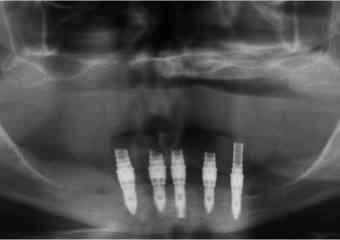

Imagens dos implantes inferiores e prótese fixa provisória imediata